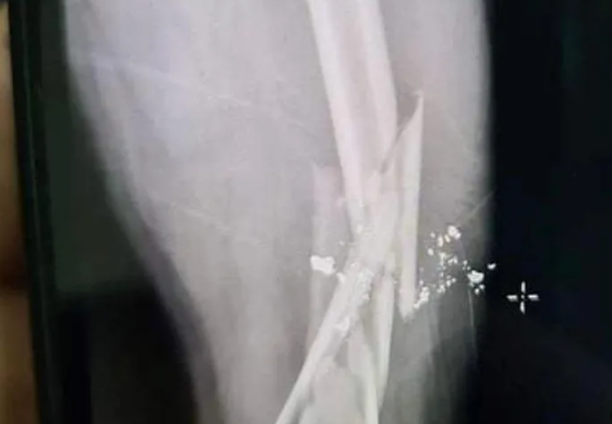

Mâu thuẫn tại bàn nhậu, người đàn ông bị bắn gãy xương đùi: Do mâu thuẫn tại bàn nhậu, Phan Công Hòa (SN 1981, trú tại huyện Kỳ Anh, Hà Tĩnh) đã dùng súng thể thao bắn anh(SN 1977, trú thị xã Kỳ Anh) khiến nạn nhân bị gãy xương đùi. Ngày 14/1, Công an thị xã Kỳ Anh cho biết đang tạm giữ Hòa để điều tra, làm rõ.